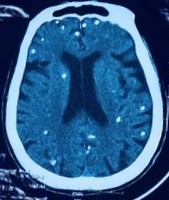

Bà được chuyển lên từ cơ sở y tế tuyến dưới đến Bệnh viện Trung ương Quân đội 108 vì rối loạn ý thức đe dọa suy hô hấp. Hình ảnh cắt lớp vi tính sọ não và X-quang ngực cho thấy rất nhiều nốt cản quang trong nhu mô não và dưới da vùng ngực - bụng. Một vài u cục với kích thước tương ứng có thể sờ thấy dưới da vùng ngực và cánh tay của người bệnh.

ThS.BS Nguyễn Sỹ Thấu, khoa Hồi sức Truyền nhiễm, cho hay xét nghiệm kháng thể IgM âm tính với sán dây lợn, song các tổn thương trên X-quang cho thấy có thể người bệnh trước đây bị nhiễm ấu trùng sán dây lợn, sau đó các nang sán trở nên vôi hóa và tồn tại lâu dài trong tổ chức. Người bệnh được điều trị theo phác đồ, ra viện tiếp tục điều trị theo tuyến.

"Nang sán dây lợn có thể tự thoái hóa hoặc bị vôi hóa, tạo nên hình ảnh cản quang phát hiện được trên phim X-quang như bệnh nhân trên", bác sĩ Thấu nói.